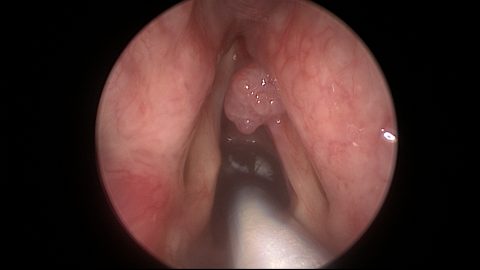

Picture of early laryngeal cancer picked up due to a change in voice